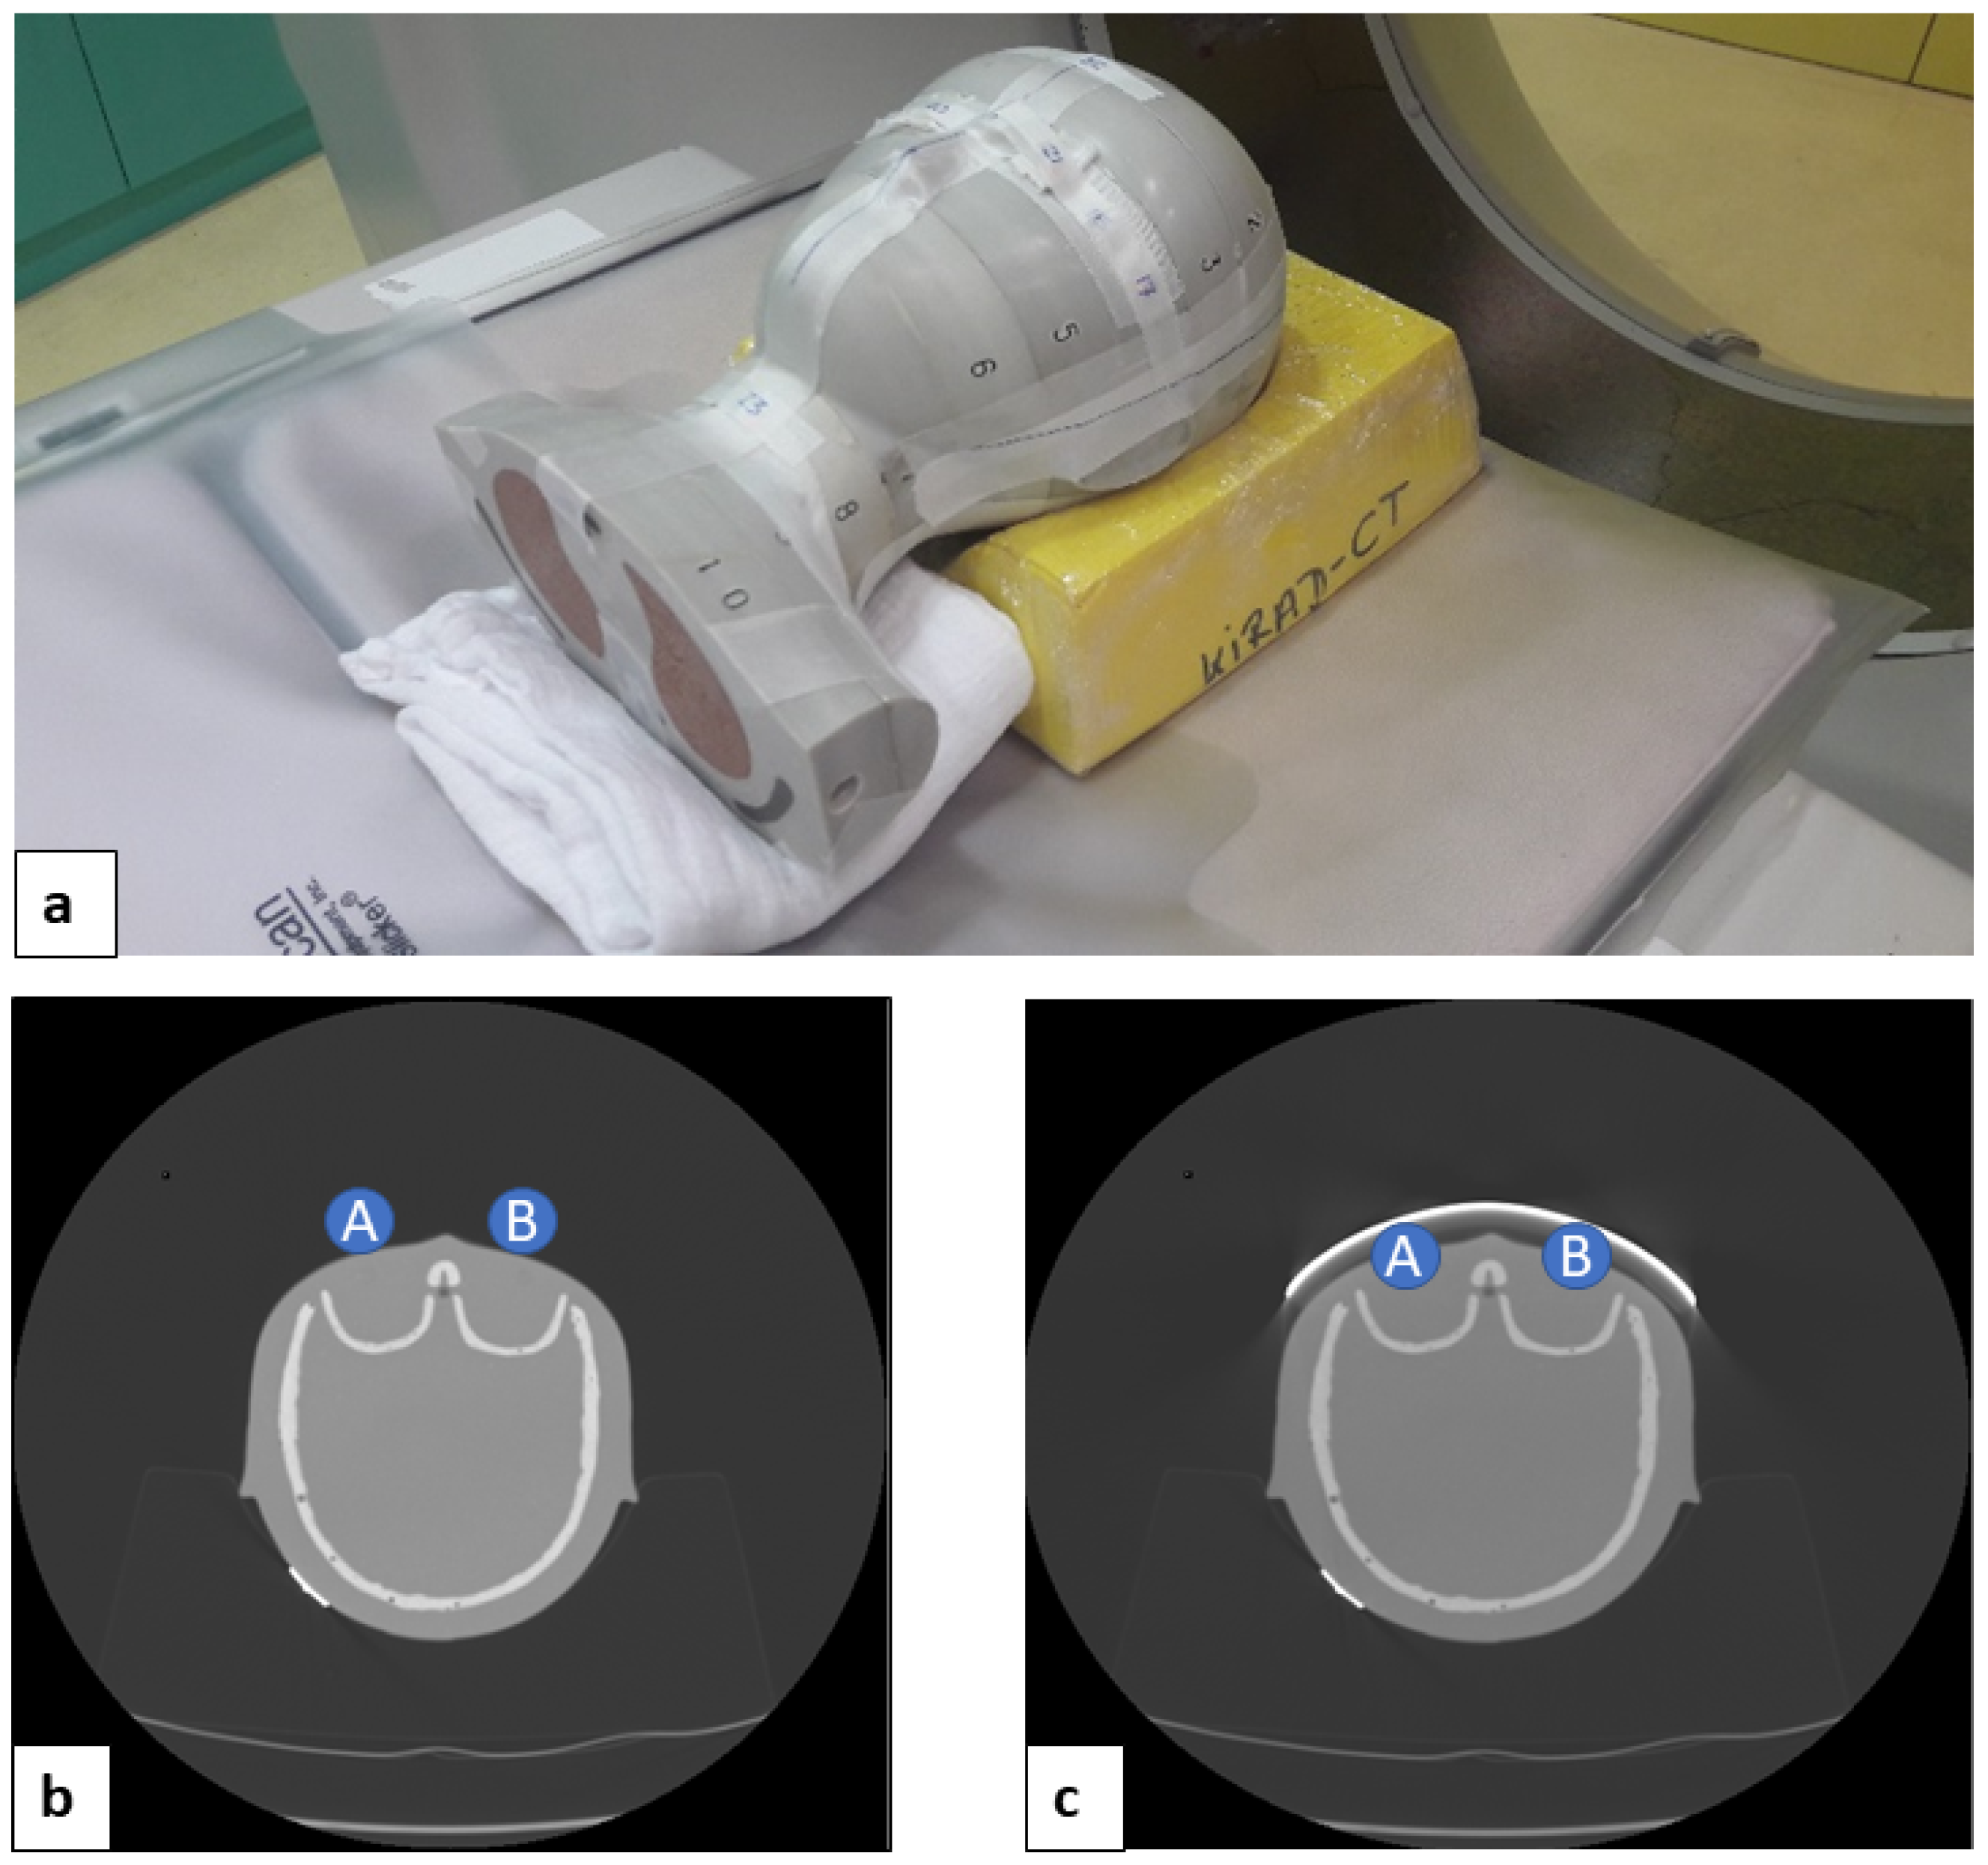

An anthropomorphic pediatric phantom (CIRS ATOM® phantom, pediatric 5 years, 110 cm, 19 kg, Computerized Imaging Reference Systems, Inc., Norfolk, VA, USA) was used. After the localizer CT radiograph was acquired, a 1.27 mm thick bismuth shield (14 × 3.5 cm, Somatex, Berlin, Germany) was placed over both phantom lens areas (Figure 1).

Figure 1.

Positioning of the pediatric head phantom within the scanner (a) CT axial scans without bismuth shield (b) and with bismuth shield (c) (measurement points: A, right lens; B, left lens).